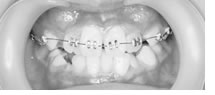

片顎のマルチブラケットで改善した9歳症例

前歯部分の凸凹は上下とも重度であった。乳歯の虫歯も多く、歯磨き練習も重要でした。